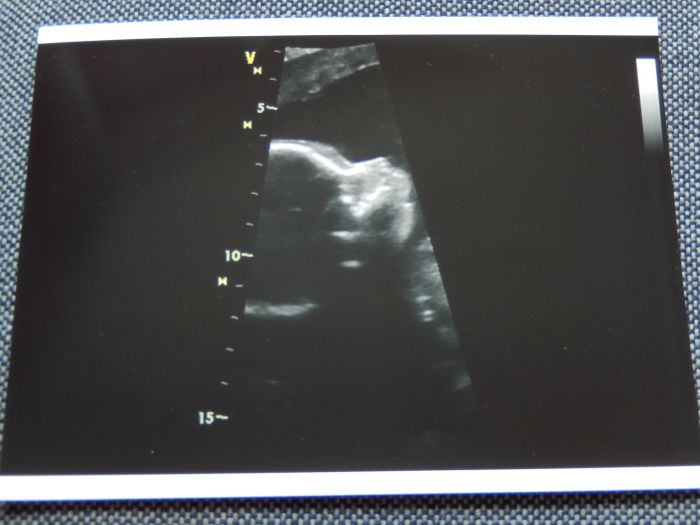

A teď to nejdůležitejší (teda pro mě

) - včera jsem byla v Gennetu na velkém ultrazvuku a všechno je v naprostém pořádku

Hrozně se mi ulevilo

Malá nám krásně ukázala, že je holčička (to by poznal snad i blbej

). A jako správná dáma se nechtěla nechat zvěčnit, pořád si dávala ručičky na obličej - asi si budeme muset počkat na originál v říjnu

V příloze přikládám aspoň profilovou fotečku obličeje